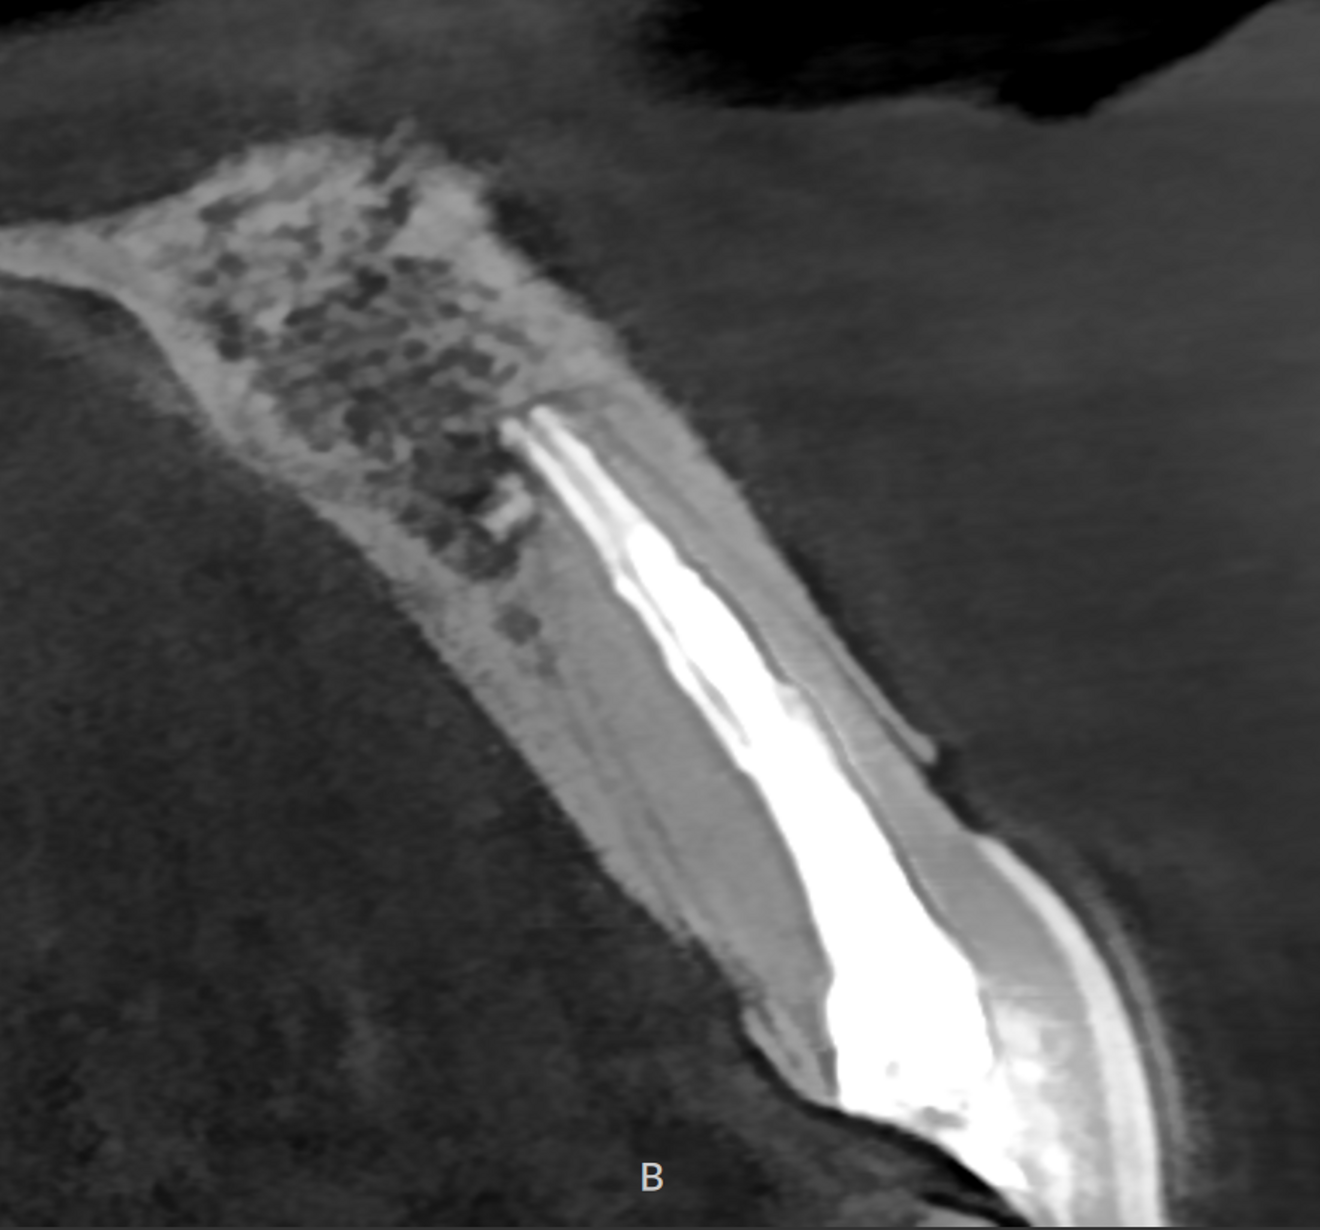

Zero apicectomy, the art of combining root canal treatment and microsurgery to preserve tooth integrity and no longer removing the apex, has been proved a very successful technique not only in preserving the tooth structure but also in recreating a new periodontal ligament where the bone can grow vertically—an idea that was impossible before—in order to save the natural teeth, a new approach in endodontic microsurgery. In a trauma case in which there was an absence of cortical bone and apical bone around the mandibular central incisors and a very deep pocket reaching the apical area, a zero apicectomy and a root canal treatment were done, and 18 months later, against all odds, the bone had grown vertically, covering the buccal part of the root almost completely, and the apical bone was completely restored (Fig. 8).

Figs. 8a–f: Absence of cortical bone and apical bone around both central incisors (a & b). Nine-month follow-up radiographs (c & d). Eighteen-month follow-up radiographs (e & f).